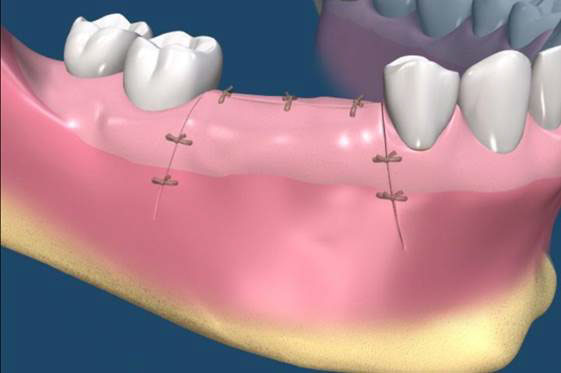

植牙的患者,由於有不同的骨缺損,因此大都需要補骨牙周固定,常見術式有幾下幾種:

拔牙後的齒槽吸收往往造成植牙和膺復上的困難。骨脊保存術是一項用來在牙齒拔除時最小化齒槽吸收和最大化骨形成的術式。臨床上,保存牙齒的方法很多,包括拔牙時盡量減少對周圍齒槽骨或黏膜的傷害,使用軟或硬組織移植,或合併使用再生膜和骨移植。病患於拔牙前經過仔細的評估後,採用骨脊保存術可以減少拔牙後齒槽骨的吸收,並有效的維持齒槽的外形。(圖04-08)

圖04

圖05

圖06

圖07

圖08